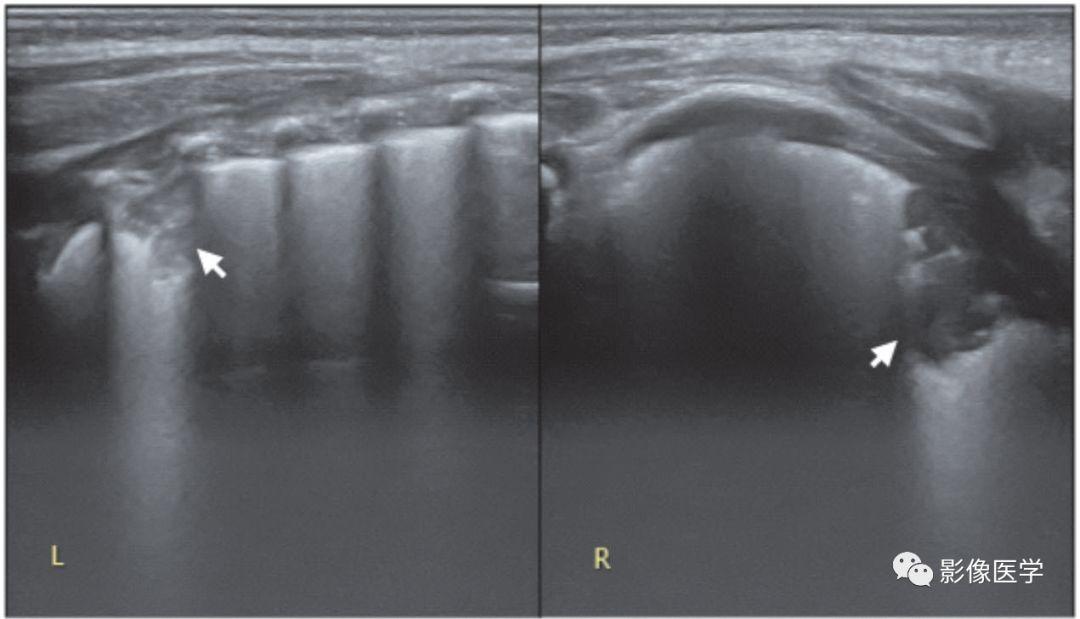

图6-27 轻度肺炎的超声表现:胸膜下实变伴左侧胸腔积液

胎龄37周,宫内窘迫伴出生时窒息,出生后轻度呼吸困难。肺脏超声显示左肺弥漫性胸膜下局灶性实变,胸膜线模糊或消失,并可见明显胸腔积液。由此可见,轻度肺炎可仅有局灶性的小范围实变。